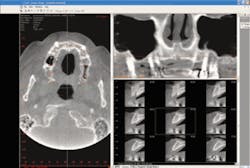

Dr. Gowey: In my 30 years of dental practice, there’s never been anything like the i-CAT for diagnosis. Cone beam CT is revolutionizing the way treatment-planning is done. With cone beam technology, dentists can perform 3-D diagnoses versus traditional panoramic and cephalometric flat film. Patient images in 2-D are distorted and magnified. These images often make it difficult for the practitioner to locate critical anatomies, pathologies, and other important anatomical concerns because they are not visible in the scan. Cone beam 3-D imaging allows dentists to see a patient’s anatomy in all dimensions by creating a 360-degree analysis. These images allow dental professionals to achieve a complete makeup of the human jaw, face, and associated structures, which leads to greater accuracy, precision, and efficiency in diagnosing and treating patients.

In orthodontics, instead of relying on flat cephalometric and AP views, CBCT 3-D allows asymmetries to be visualized, making diagnosis more accurate. I can view the entire skull on a computer screen, rotate it, and superimpose the soft tissue. For instance, I can see a periapical lesion hiding behind the root that doesn’t show up on a periapical radiograph very well. I can clearly visualize impacted teeth. I can view the inferior alveolar nerve in relation to the roots of the teeth, and can clearly delineate endodontic lesions.

There is also the ability to see calcifications in major blood vessels in the upper neck and visualize sinus anatomy. The temporomandibular joints can be examined in 3-D. Compare this to a tomogram, which gives single slices through a joint so the whole joint can’t be seen. With CBCT, we can examine the bony joint surfaces and shape in detail. Cone beam scanning also benefits patients, exposing them to significantly less radiation than a medical CT scan.

As a result, I’ve been able to find the unexpected well in advance of a procedure, shorten treatment-planning time, and increase diagnostic accuracy and surgical predictability. The i-CAT replaces a cephalometric and panoramic X-ray machine. Since it is digital, the images can be manipulated to change contrast and brightness and apply filters to help you find what you are looking for. There is so much information available to you from one scan compared to conventional radiography. One scan gives you an image of the maxilla, mandible, TMJ, sinuses, nasal cavity, and area back to the cervical spine. You can see root positions in the bone for orthodontic treatment, bony dehiscences and fenestrations, abcesses draining into the maxillary sinus, impacted tooth locations, salivary stone location, and many other pathologies in the maxillofacial area.

Very accurate measurements can be made directly on the images. Bone density can be measured in any area on the scan. TMJ mapping is very easy. A panoramic view is normally mapped and can be done separately for the maxilla and mandible to improve image clarity if needed due to malocclusion or jaw-size discrepancy.